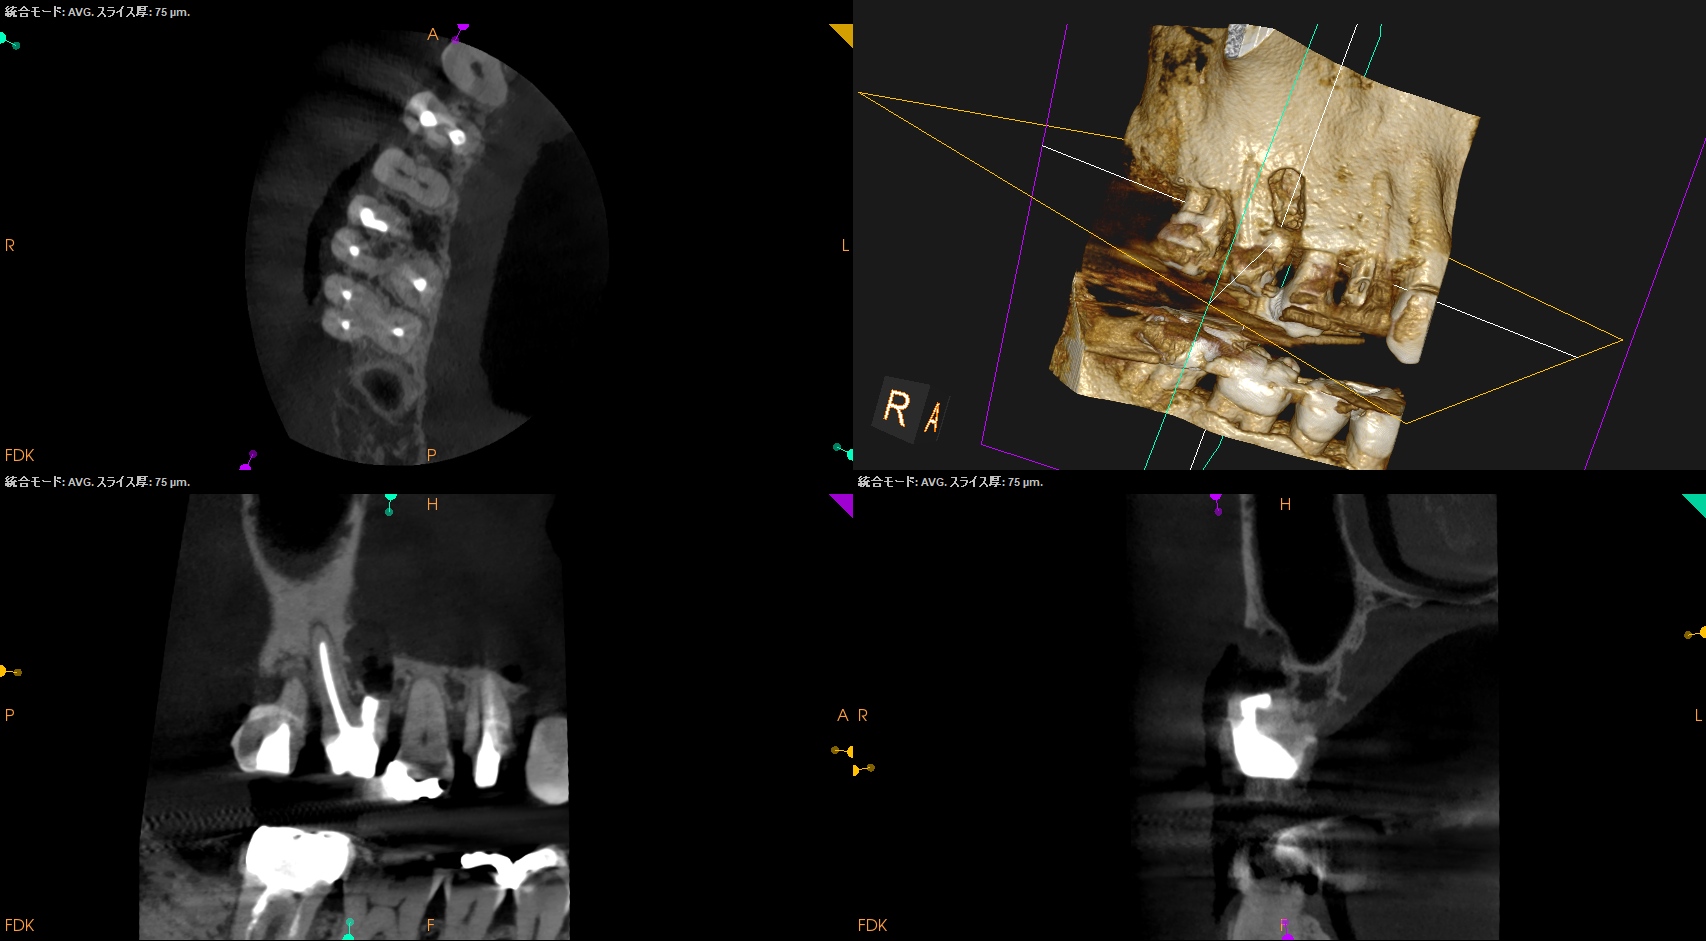

さらに切断部位から4mm, 頬舌的幅径が6.7mm必要だが再切断し逆根管形成・充填を試みることにした。

その際は

人為的にApico-marginal deffectを作らないように注意する必要があるだろう。

再切断したら…

Apico-marginal deffectを人為的に作成してしまった。

ここで一気にテンションが下がるが、以下のように終わらせた。